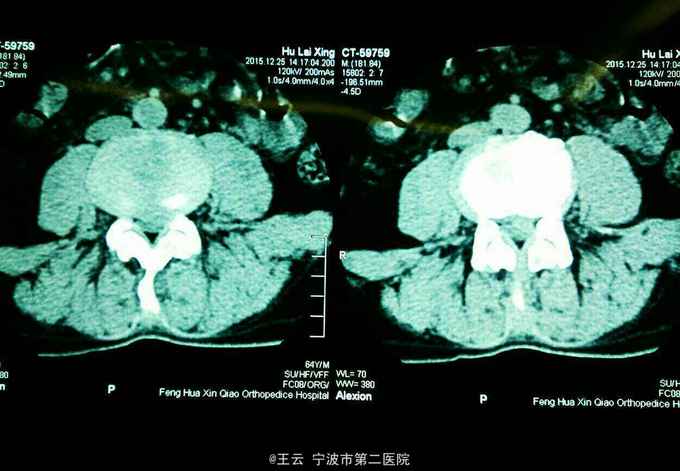

腰3/4椎间盘脱出向下高度游离

患者,女,41岁,因“左下肢放射痛麻木三个月”入院。三个月前有过度劳累史。

查体:左小腿前内侧感觉减退,左侧踝背伸肌力4级,左下肢直腿抬高40度阳性,4字征阴性。

诊断:L3/4椎间盘脱出 治疗:经椎间孔入路椎间孔镜下髓核摘除,射频消融